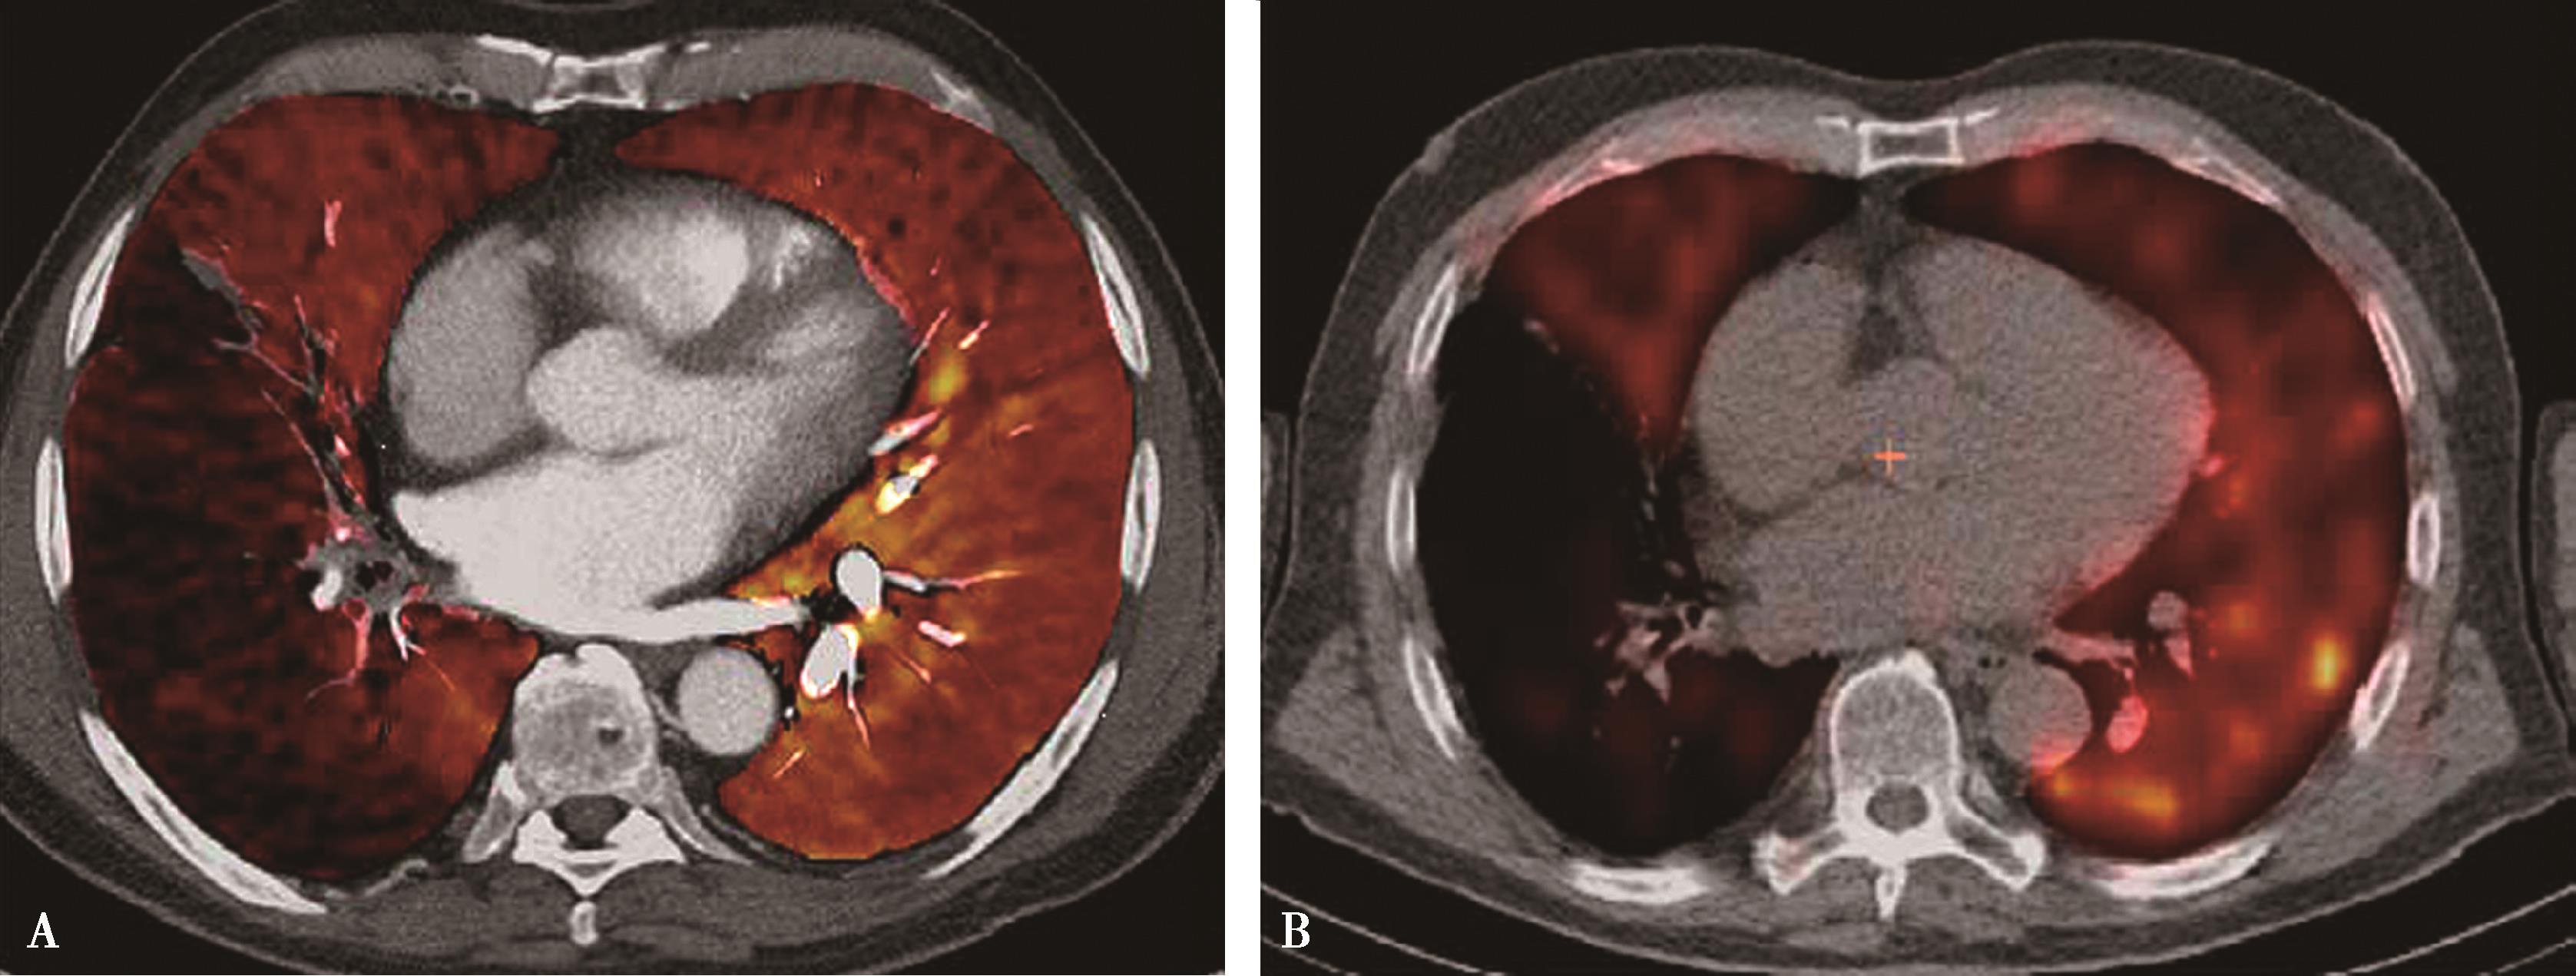

图8-1-6 右肺下叶外基底段栓塞;能谱成像得到肺碘基物质图,反映栓塞分布、梗阻呈低灌注、程度